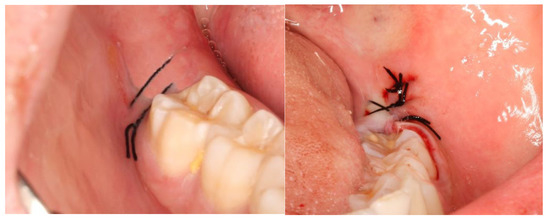

2. Materials and Methods

2.2. Definition of the Variables in Study and Follow-Up of Patients

3. Results